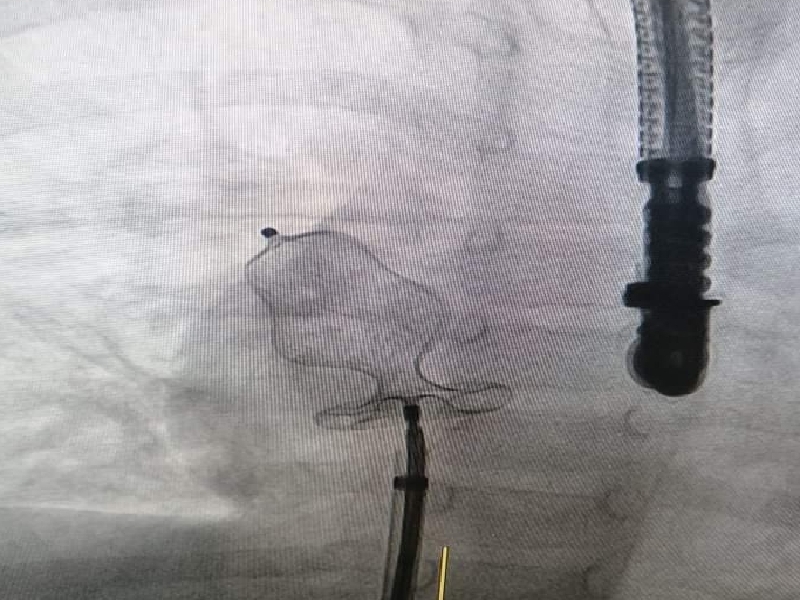

(ASD CLOSURE

وتحتاج الى عملية جراحية لاغلاق الفتحة بين الأذين الأيمن والأذين الأيسر وقد اجري هذا العمل الطبي التداخلي interventional therapy دون إستخدام الجراحة عبر تقنية البالون المساعد من أجل وضع الجهاز في مكانه الصحيح بدل من اجراء عملية جراحية لتعتبر هذه العملية من العمليات النادرة لهذه المرحلة العمرية حيث تنفرد مستشفى الاعظم بأطباء متخصصين ينفذون هذا النوع من العمليات ولجميع الاعمار